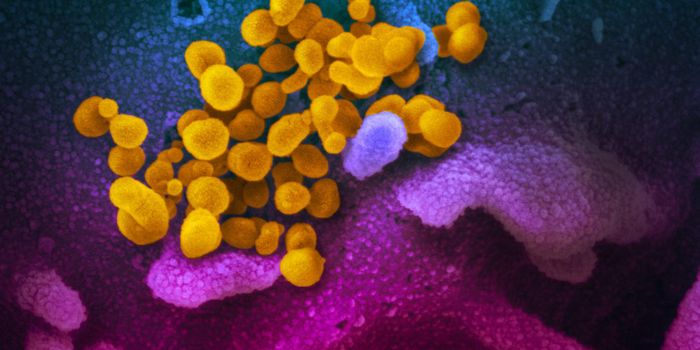

MAY 03, 2020Genetics & GenomicsThe origin of SARS-CoV-2, the pandemic virus that causes COVID-19, has become politicized as leaders seek to place blame ...

JUL 06, 2020MicrobiologyThe pandemic coronavirus has caused a wide range of different symptoms, and as time goes on, we may find that it can hav ...

JUL 05, 2020Cell & Molecular BiologyThe pandemic virus SARS-CoV-2 enters the body through the respiratory system to cause the illness COVID-19. But we know ...

JUN 29, 2020MicrobiologyVaccines that contain live attenuated viruses may be giving people some protection from serious cases of COVID-19 that i ...

FEB 22, 2021MicrobiologyReporting in Science, researchers have created an antiviral nasal spray that could help us get the COVID-19 pandemic und ...

SEP 01, 2021MicrobiologyIt's been generally assumed that people who get infected with SARS-COV-2 will develop antibodies to the virus, which cau ...

MAR 18, 2020MicrobiologySARS-CoV-2 is a coronavirus that causes an illness called COVID-19. There are now well over 210,000 confirmed cases worl ...